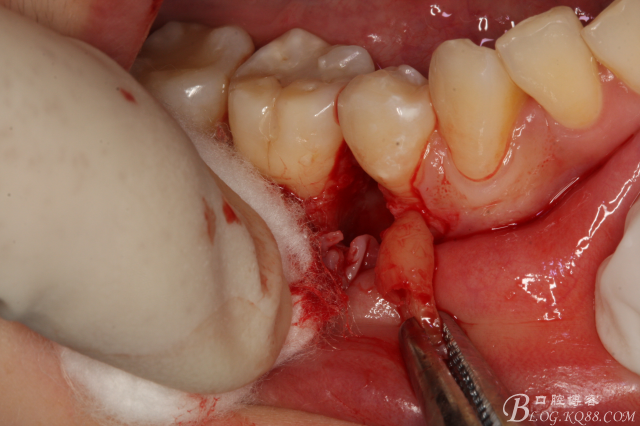

圖5.局部麻醉下、在44近中做垂直小切口,切口不要超過膜齦聯(lián)合。

圖6.齦溝內(nèi)水平切口

圖7.翻小瓣。暴露45牙根斷面

圖8.高速球鉆去骨約3mm.

圖9.暴露45頰側(cè)根面約1/2.牙根與44、46牙根緊緊相鄰。無法直接用挺。